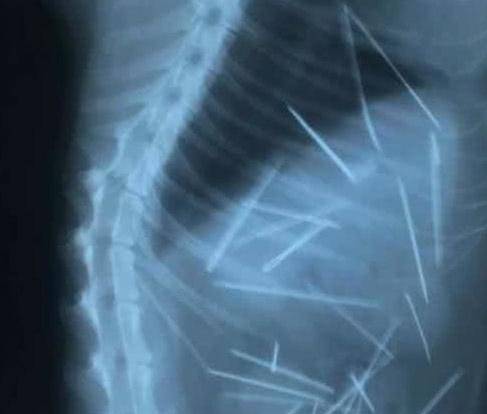

女子感觉相当奇怪,于是就带猫咪去宠物医院做检查,怕猫咪的身体有其他毛病。在宠物医院里,医生给猫咪做了一个x光的外景拍摄,发现了一个很极为恐怖的事情,把女子和医生一众人都吓,原来猫咪身体里有很多的针,那些针密密麻麻爬满它的身体,这个表面上但却很健康最好的猫咪,每天晚上都要能够承受那些个因为自己的五脏六腑的伤害,它在这一瞬间活动,每个动作,都会让自己无比疼痛。

看见自己的猫咪给予如此样的折磨,不由得都流泪了,另外也感觉到很惊诧,要知道这样的场景自己也就没看到过。不知道是什么好人这般如此狠心,对一个猫咪下此毒手。而后医院对猫咪并且了手术,这次手术经历了四个多小时,在医生的精挑细选手术下,将这一根根的针所有去除,这些过程很漫长而艰辛,猫咪也有过住了那样的难过的折磨。